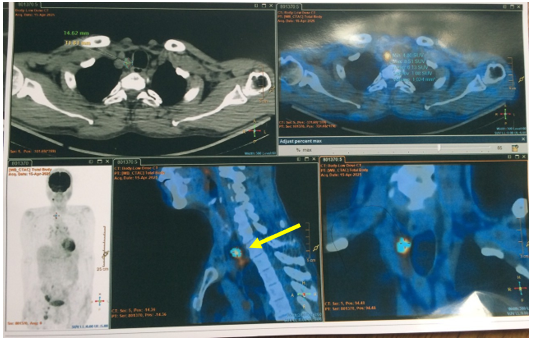

– PET/CT (Tháng 03/2025): Không thấy tổn thương tăng hấp thu FDG khu trú bất thường tại hạ họng. Hình ảnh hạch nhóm 1R, kích thước 12x15mm, tăng chuyển hóa glucose, khả năng do di căn. Đề nghị đối chiếu với mô bệnh học. Hình ảnh tổn thương giảm tỉ trọng kèm vôi hóa kích thước ~33x50x39mm, tăng chuyển hóa glucose ở hạ phân thuỳ VII gan, tương ứng với tổn thương gan đã nút mạch, theo dõi tiến triển. Hình ảnh nhiều hạch ở dọc theo động mạch chậu chung và chậu ngoài phải, bẹn phải, tăng chuyển hóa glucose. Đề nghị đối chiếu với mô bệnh học. Chưa phát hiện hình ảnh tăng hấp thu FDG bất thường, khu trú tại các vị trí khác trên xạ hình PET/CT toàn thân.

Hình 5: Hình ảnh hạch nhóm 1R, kích thước 12x15mm, tăng chuyển hóa glucose (SUV max 8,5), khả năng do di căn. (mũi tên vàng)

Hình 6: Hình ảnh hạch bẹn, kích thước 14x29mm, SUV max 8,9 (mũi tên vàng)